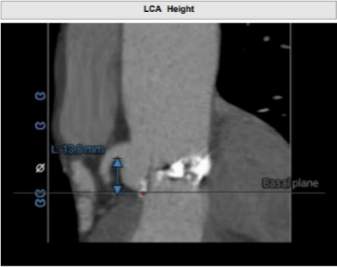

• 左冠高度8.3mm,左窦瓣叶长度10.2mm,瓣叶明显增厚,应注意术中冠脉闭塞风险。

患者左冠脉开口高度11.0mm,左冠窦瓣叶长度14.3mm, 瓣叶明显增厚,有轻度钙化。应注意术中有冠脉闭塞风险。患者未见明显心室隔膜部,新发的房室传导阻滞风险较高。